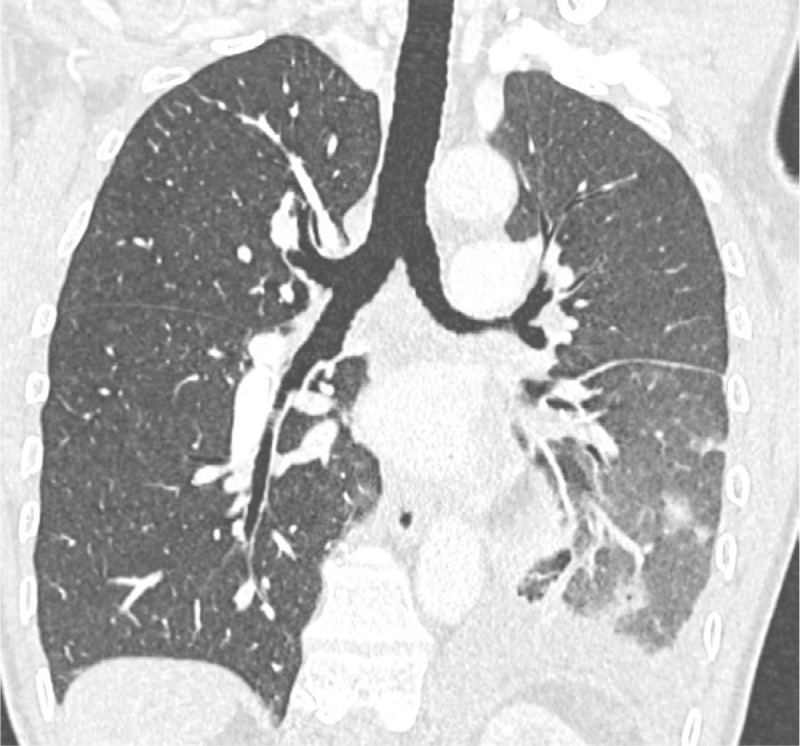

Teaching point: Description of a new radiological sign named "pulmonary hilar cavernoma" in a case of unilateral total pulmonary vein thrombosis.